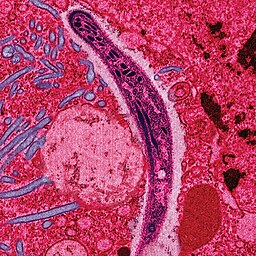

The sporozoite stage of the malaria parasite. 📷 Image Credit: Ute Frevert; false color by Margaret Shear